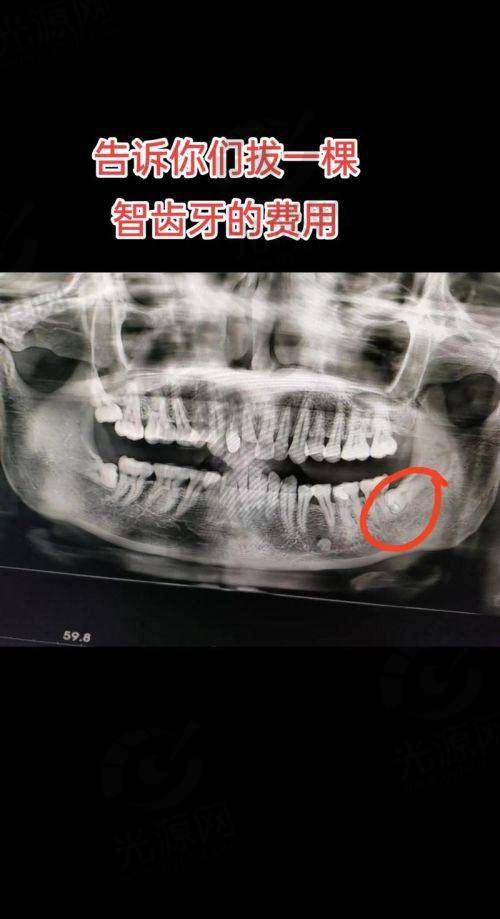

智齿拔牙后窟窿恢复图,智齿拔牙后恢复过程与图片解析,7天到30天牙洞愈合状态详解

智齿拔牙是许多人在成长过程中的一道难关,而了解智齿拔牙后窟窿修复图,可以帮助您更好地应对这一过程。智齿的生长常常伴随着疼痛和不适,尤其是当它们位置不正或受阻生长时,拔除智齿成为了必要的选择。 在拔牙后的修复过程中,患者往往会关心拔牙后的伤口愈合情况,以及正常修复的标准。本文将详细介绍拔智齿后的伤口愈合情况,通过智齿拔牙后窟窿修复图,帮助您了解拔牙后7天、14天、30天的伤口状态和修复进程。并且,我们还将结合医学数据和实际实例,为您提供关于拔智齿后修复的科学认识和行动指南。通过对这些信息的深入理解,您将能更有信心地渡过拔牙后的修复阶段。

智齿拔牙后窟窿修复图的重要性

在智齿拔牙后,伤口的愈合是每位患者更为关心的事情之一。智齿拔牙后窟窿修复图能够直观展示拔牙后伤口在不同时间阶段的愈合过程,帮助患者更清晰地了解自己的修复情况。研究显示,在拔牙的后的第一个星期,伤口的自我愈合已开始慢慢展现,通常在这一阶段患者会感到疼痛和肿胀,而这也是完全正常的。

通过观察智齿拔牙后窟窿修复图,患者可以了解到,伤口周围组织的再生与愈合过程是一个逐步的过程。在拔牙后的7天内,伤口周围的组织会开始形成一种叫做肉芽组织的物质,这是愈合过程中非常重要的一步。